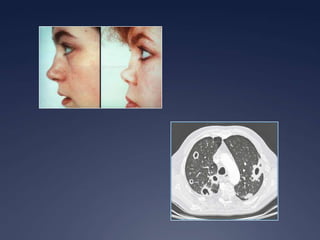

Granulomatose avec polyangéite

 Signes généraux

 Plus frustre que d’autres vasculites

 Asthénie, fièvre, arthralgies, arthrites

symétriques, myalgies, amaigrissement

 Atteinte ORL

 70% des patients

 Obstruction nasale persistante

 Sinusite à répétition, croûteuse, hémorragique

 Otite moyenne séreuse, hypoacousie

 Atteinte des cartilages du visage

 Pseudotumeur orbitaire, exophtalmie

 Sténose sous-glottique

 Atteinte pulmonaire

 Multiples présentations

 Nodules souvent excavés avec paroi épaisse

 Infiltrats pulmonaires

 Sténose bronchioles

 Hémorragies intra-alvéolaires 8-30%